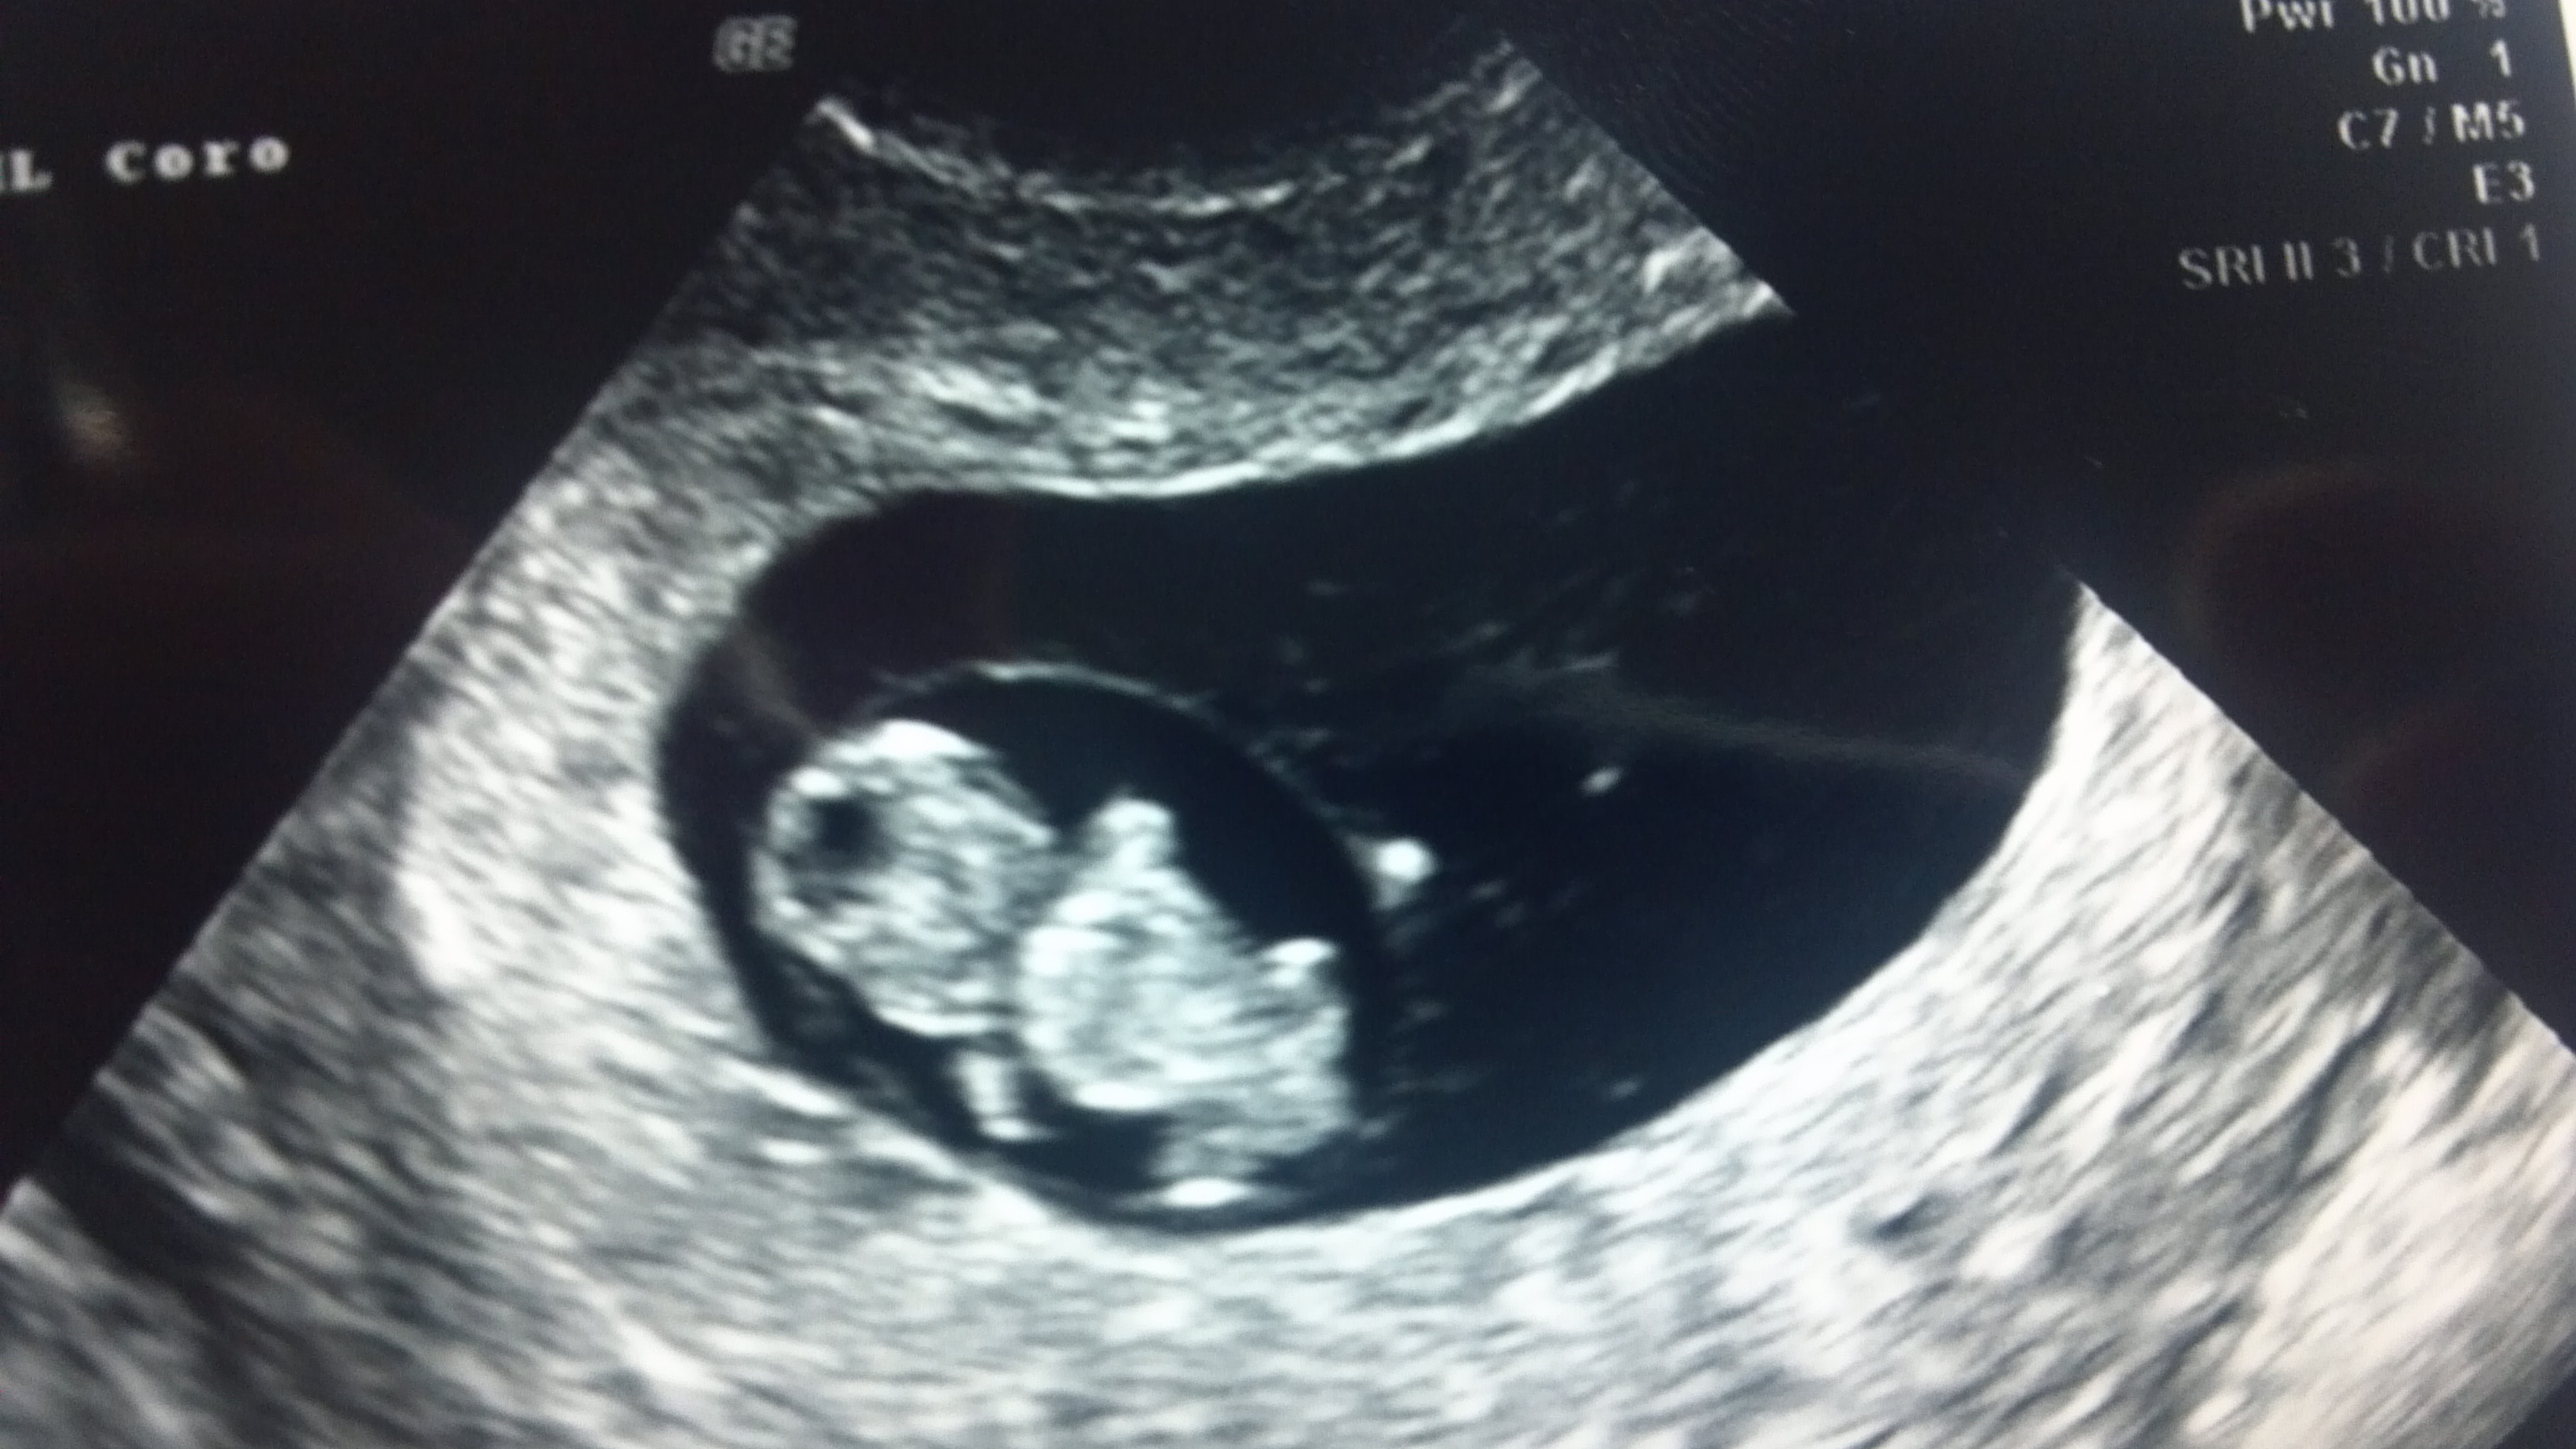

How Far Along? 10 weeks and 6 days

Gender: Mystery baby! It will stay a mystery until I deliver. 🙂